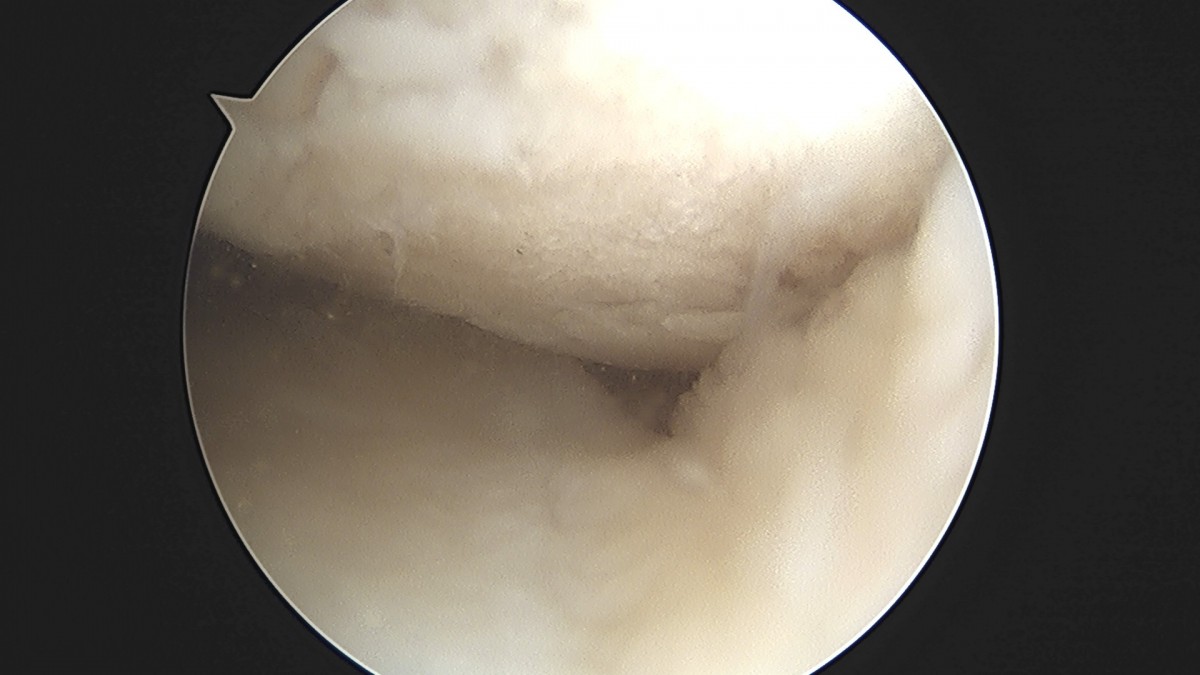

정지영원장님 무릎 반월상 연골판 절제술 이영O 환자

dae765e4d9ac96aee867c9d6292d8784_1758009376_0053.jpg